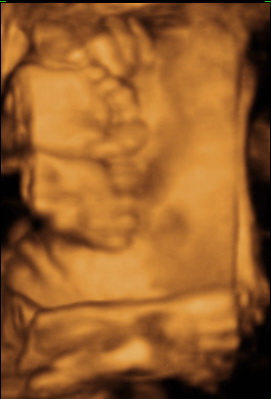

Vasárnap voltunk, bár sok dolgot nem láttunk. Kimondottan ellenzi a baba, ha meg akarjuk nézni. Engem az érdekelt, hogy mekkora lehet. Méretei alapján 1,6 kg. Ici-pici :-) Azt mondták max. 3,2-re nő meg a 40. hétig. Csöpp baba lesz. Képet nem nagyon tudott a néni csinálni, mert gombóc volt. A 20 ujjacskáját az arca elé pakolta. Kis pukkancs lett. (Hűűű, és a köldököm de fájt közben! Meg kellett kérnem, hogy inkább másfelé kalandozzunk.)

Kép

Örülnék neki, ha hamarosan megfordulna. Bár nem tudom általában mikor szoktak, de ő nagyon nem akar :(

Itt vannak azok a picike ujjak :-) Biztos ki tudjátok venni, de a bal kezecskéje kicsit közelebb van, ezért elszeletelődött :-) Hihetetlen, hogy így elférnek az emberben. Ezek a képek készültek utoljára, a legközelebbin már rózsaszín lesz!

almi